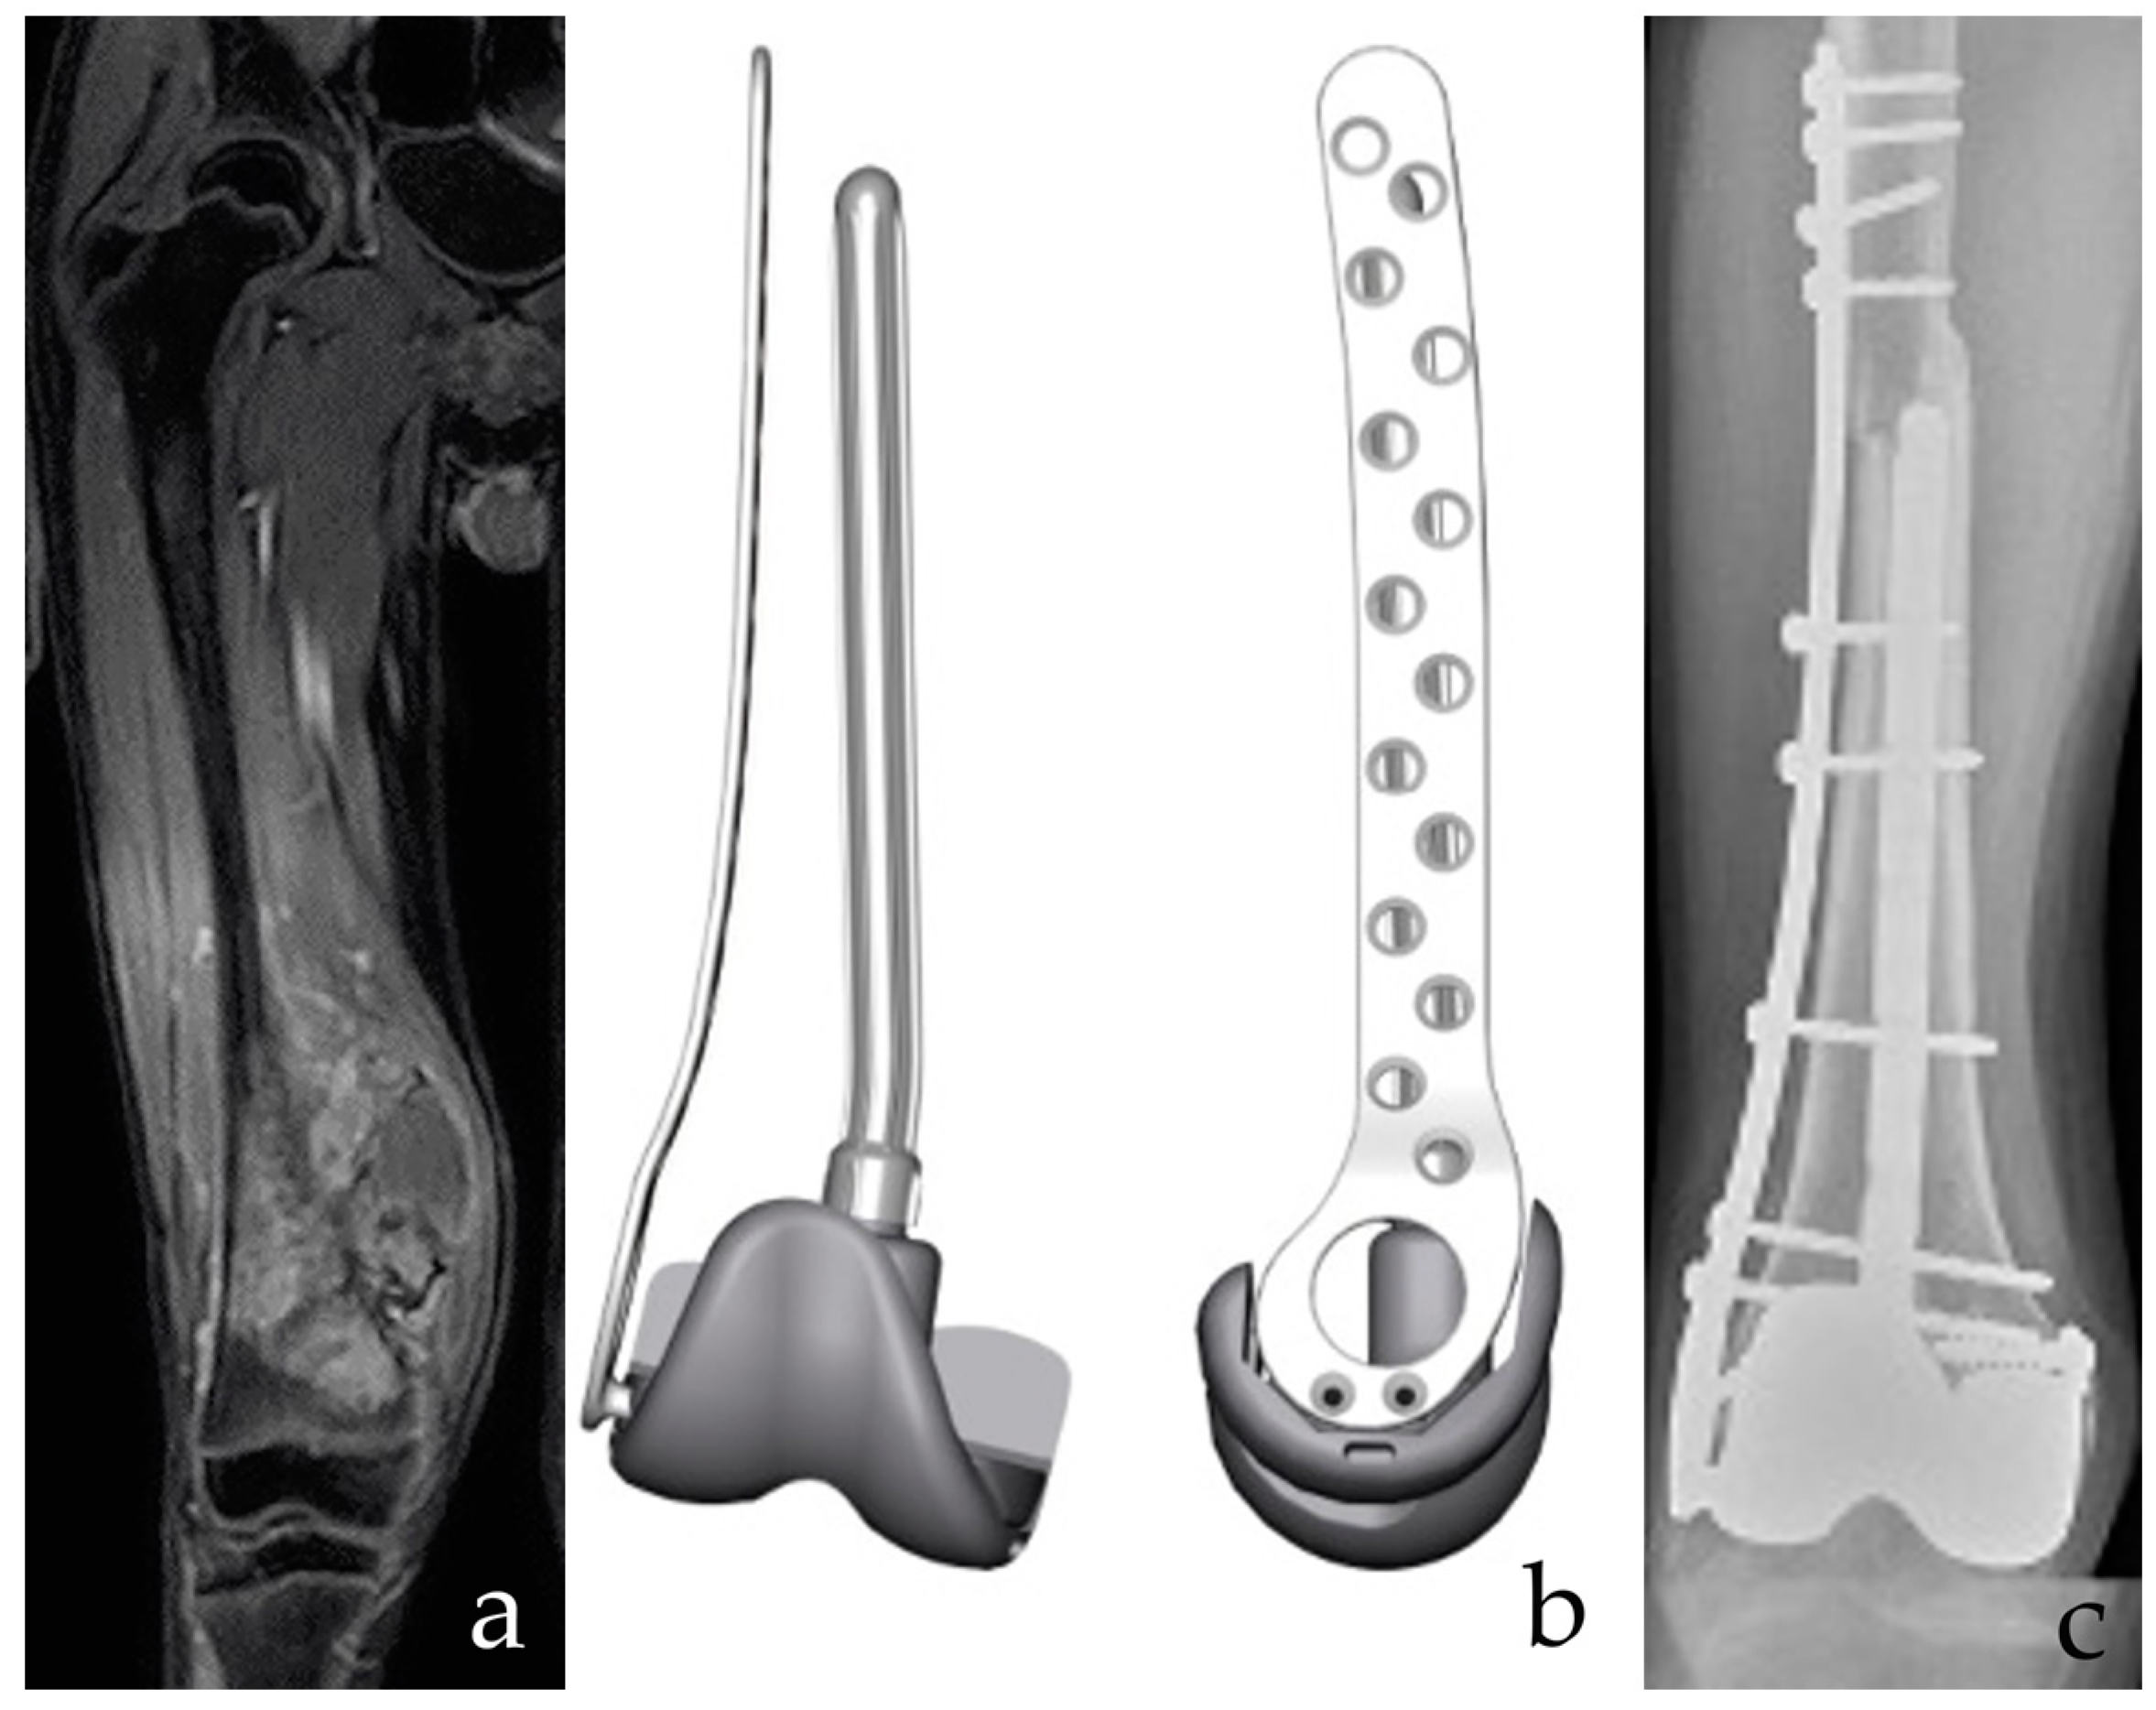

Figure 2.

(a) A 12-year-old male patient with osteosarcoma of the distal femur after neoadjuvant chemotherapy. Intrarticular resection. (b) The planning of a custom-made, 3D-printed plate combined with a resurfacing prosthetic implant and intramedullary stem. Both the prosthetic surface and the intramedullary stem are removable in case of failure of the allograft, with bone stock retaining for conventional Allograft Prosthesis Composite (APC). (c) APC with bone massive allograft of the distal femur. Bone stock reconstruction and sparing of the proximal tibia growth plate are provided. The collateral and cruciate ligaments are functional. Postoperative imaging confirms fusion of the osteotomy line and stable implant positioning.